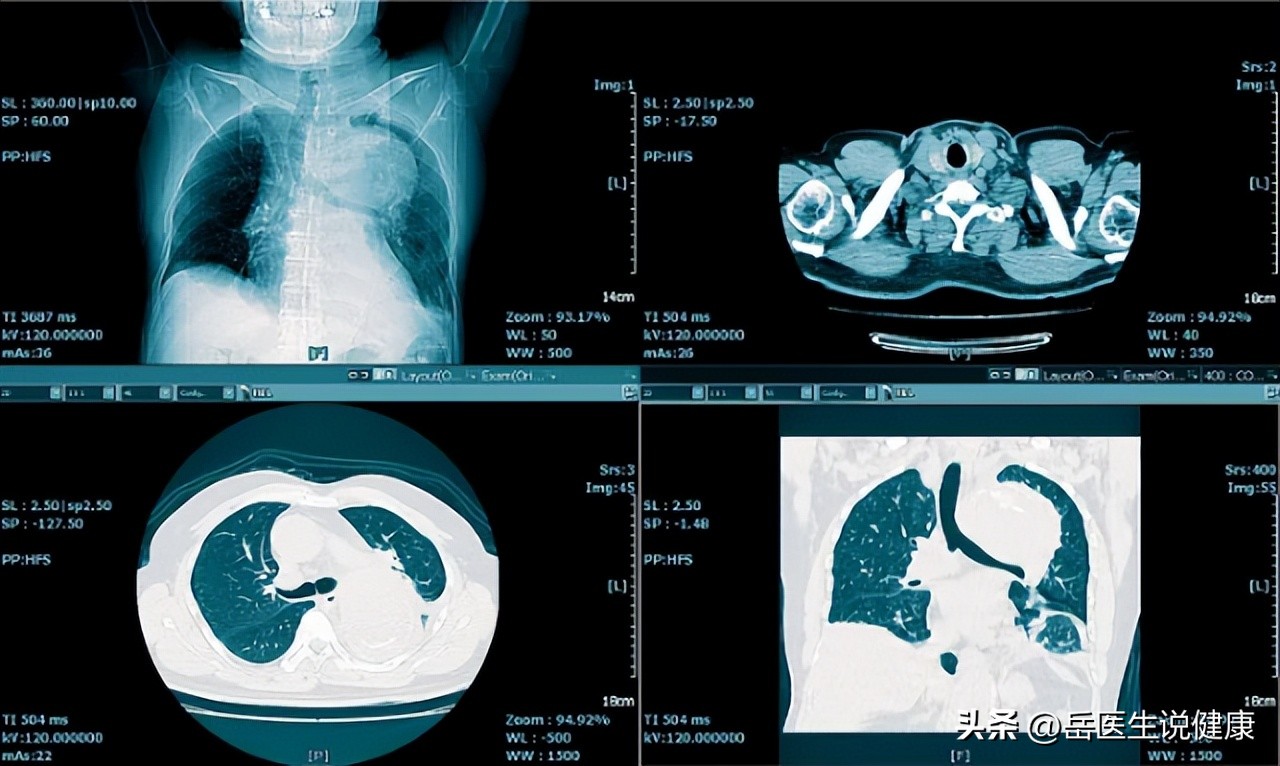

但最近半个月李先生右肩部和上肢疼痛明显,穿衣、洗澡都感觉疼痛难忍,有时晚上被疼醒,不易再入睡, 李先生的家人见情况不妙,便专门陪他到当地专科医院求治。这次,李先生按照医生的要求拍了颈部、胸部X线片,医生仔细地审阅后,终 于发现右肺尖部的胸膜稍有增厚 ,这一异常使医生进行胸部CT扫描,最后,肺癌的阴影终于进入了医生的视野。

早期主要的筛查方法,主要是是胸片与痰液细胞学检查。X线胸片方便经济,患者无痛苦,但缺点是不能发现直径小于1cm的肿物。

对某些症状典型、高度怀疑为肺癌的患者, 在X线胸片与痰液检查结果均为阴性时,可以直接行CT检查确诊 ,因为有时肺癌位于肺的中央部位,这阴影往往被心脏和大血管的阴影掩盖,所以单靠胸部X线检查容易很造成误诊。气管镜检查可以取到组织行病理学诊断。

临床中,肺癌患者除了上述的肺部症状外,还有许多肺外的症状,最常见的是 杵状指和肥大性骨关节病 ,如果发现此类问题应进行胸部X线或CT检查,以排除肺癌的可能。